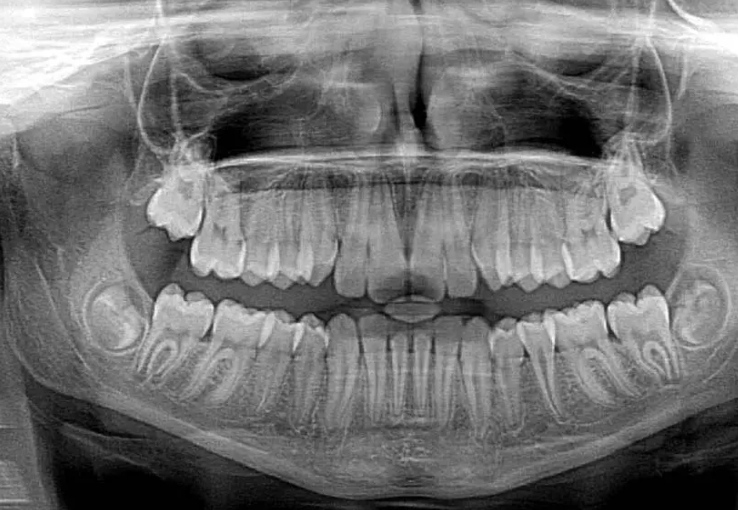

X-ray 사진 보는 법

X-ray 사진은 기본 원리를 알면 꽤 흥미로워요. 뼈처럼 단단한 조직은 방사선을 거의 통과하지 않아 흰색으로 보이고, 근육이나 지방 같은 조직은 회색, 공기처럼 비어 있는 공간은 검정색으로 나옵니다. 그래서 폐는 검게, 갈비뼈는 하얗게 보이는 거죠. 물론 정밀한 판독은 전문가에게 맡겨야 하지만, 기본적인 구조만 알아도 진료를 이해하는 데 큰 도움이 돼요.